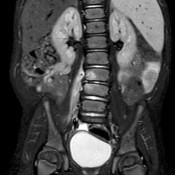

Percorsi clinici

Sclerosi epatoportale

Sparaventi C, Zago A, Di Leo G, Barbi E, Bramuzzo M.

Una nuova condizione epatica, spesso sottodiagnosticata, con una evoluzione variabile, a volte benigna, in altri casi con ipertensione portale. Rara, ma come novità da conoscere e riconoscere.